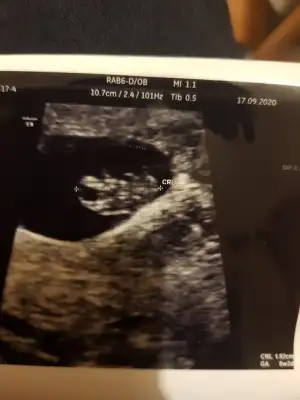

yarın benimde kontrolüm var geçen hafta rahatsızlandıgımda görmeme rağmen bende çok özledim merak ediyorum yaa hayırlısıyla sağlıkla ilerlesin inşaallah hamileliklerimiz